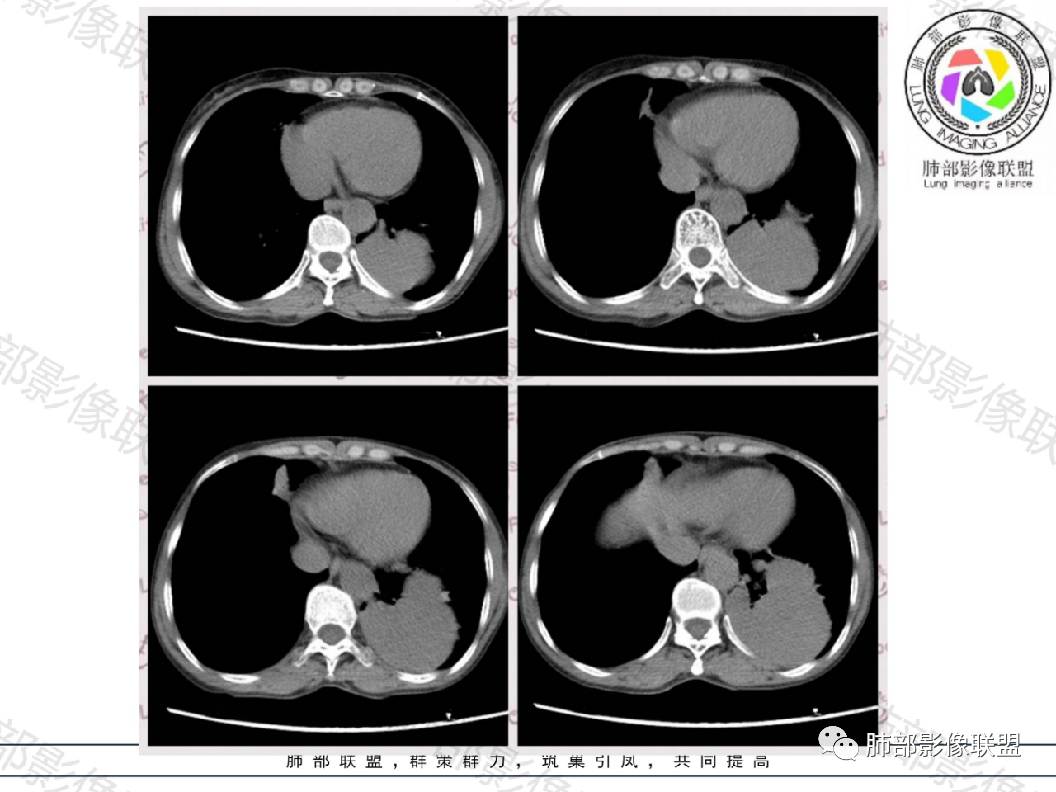

隔离常规是要考虑的,我需要看到供血血管

如果明确不是体循环供血

总体还是倾向于:肺内,囊性,先天性病变可能

膈下的体动脉供血

体循环供血

这种常规来说,供血血管是非常清晰的。

就是一个体循坏的膈下的供血,我为什么考虑先天性的,我觉得左下肺是变小的。

我担心的是有些恶心肿瘤的,它也可以是体循坏供血。

但是这么明显的少,放个待排吧,首先选择隔离征吧。